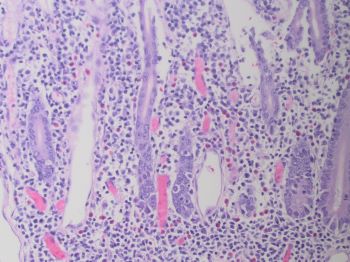

On H&E, the cytologic features of the neoplastic T-cells are typical of MEITL rather than EATL, showing greater uniformity in appearance than would be seen in EATL. Typical for MEITL, the T-cells in this case are mostly medium-sized, contain relatively round nuclei, and have inconspicuous nucleoli. In EATL, tumor cells show pleomorphism, widely varying in cytologic appearance with medium or large sized cells containing round or angulated nuclei with prominent nucleoli.